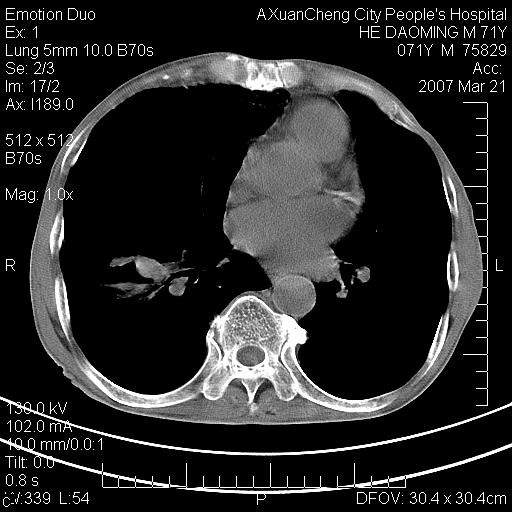

标题: CT7269:[原创] 咳嗽,咳痰,大家讨论右肺病变的部位 [打印本页]

标题: CT7269:[原创] 咳嗽,咳痰,大家讨论右肺病变的部位

右侧相当于叶间软组织样密度ct值约50hu,请大家讨论是什么性者病变

考虑:慢性支气管炎合并全小型肺气肿、肺大泡、间质纤维化、感染,右斜裂积液。

慢性支气管炎,全小叶性肺气肿,右肺上.中叶肺大泡,伴有感染.支气管扩张.

考虑慢支,肺气肿,肺大泡,间质纤维化;右侧斜裂液气胸考虑(可能因为肺大泡破裂破入斜裂所致).

1双肺慢性支气管炎并全小叶型肺气肿肺大泡2间质性纤维化3右侧斜裂积液

考虑:慢性支气管炎合并右侧全小型肺气肿、肺大泡并感染、双肺间质纤维化,右斜裂积液。

如果患者变化一下体位扫描可分辨液平与斜裂的关系。

考虑:慢性支气管炎合并右侧全小型肺气肿、肺大泡并感染、双肺间质纤维化,右斜裂积液。右侧斜裂液气胸考虑(可能因为肺大泡破裂破入斜裂所致).